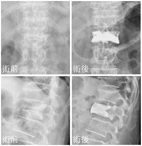

圖四:因嚴重骨質疏鬆的關係,脊椎在X光片上幾乎看不

清。經椎體成型術治療後,椎體高度得以恢復並得

到強化